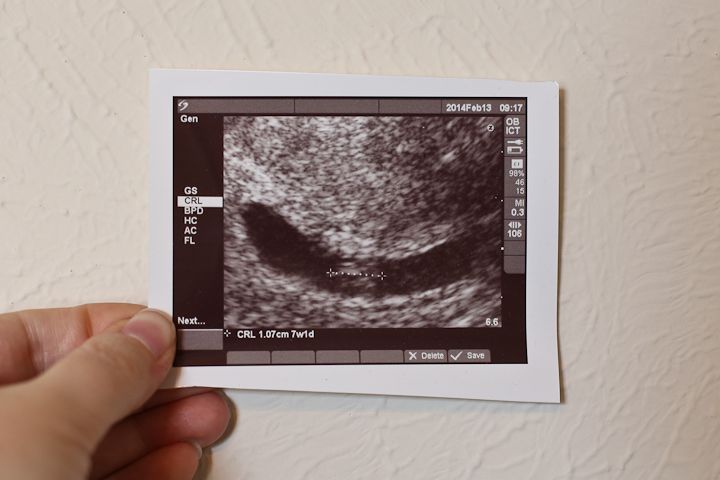

We had our first doctors appointment and got to see the baby!  It was so amazing!

The baby is tiny right now, only 1 cm long.  My due date is September 26th, but we will schedule a c-section for the week before.

We loved getting to see our baby.  I wish I could get an ultrasound at every appointment.